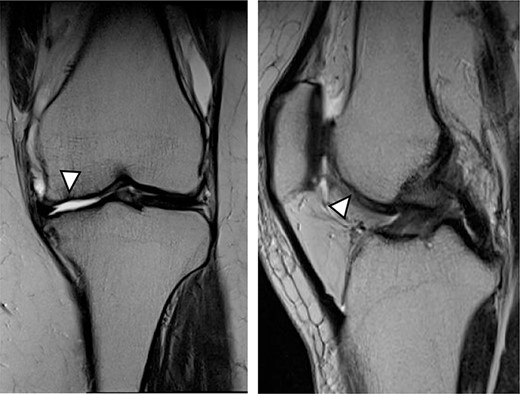

There were cartilage defects (arrowhead) in the medial femoral condyle and trochlea of the left knee (a, b).

Articular cartilage injury was shown in the medial femoral condyle (arrowhead) (2.5 × 3.5 cm; Outerbridge classification, Grade III) and trochlea (arrowhead) (1.3 × 1.7 cm; Outerbridge classification, Grade III) (a, b).

A 42-year-old female (BMI, 27.4 kg/m2) presented with 2 years of left knee medial joint pain. Active range of motion (ROM) in the left knee was from 0 to 140 degrees with no extension lag. Preoperative Tegner scores, Lysholm scores and Knee Injury and Osteoarthritis Outcome (KOOS) scores are shown in Table 1. Preoperative radiographs of the left knee joint showed mild medial osteoarthritis (OA) of the knee and hip–knee–ankle (HKA) angle of 1.5-degree varus. 1.5-Tesla MRI was performed on unit (Toshiba, Kawasaki, Japan) was used with an extremity surface coil. Proton density images were obtained using the fast spin-echo technique. A modified magnetic resonance observation of cartilage repair tissue (MOCART) system was used for the quantitative evaluation of MRI findings of the cartilage injury [15–17]. MRI showed cartilage injury of the medial femoral condyle (MFC) and trochlea of the left knee (Fig. 1).

MRI showed cartilage injury of the medial femoral condyle (arrowhead).